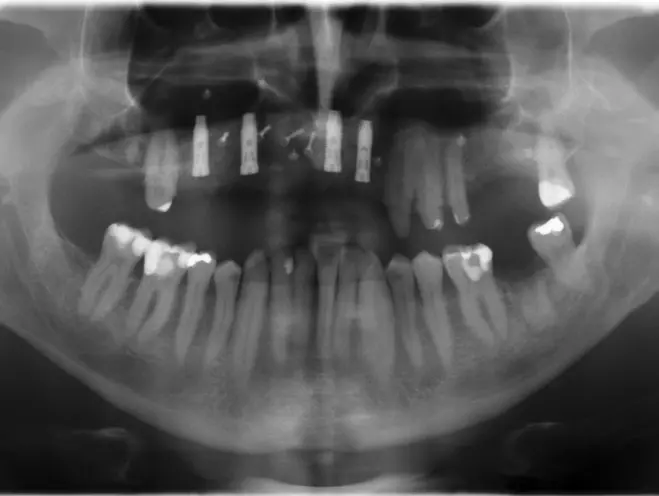

Ein 53-jähriger männlicher Patient, Raucher mit einem durchschnittlichen Zigarettenkonsum von 15 bis 20 Zigaretten pro Tag, stellte sich 2013 in unserer Praxis mit einer konservierend und prothetisch anbehandelten Gebisssituation mit Schaltlücke im linken Oberkieferseitenzahnbereich vor. Durch umfangreiche parodontale, chirurgische und augmentative sowie implantologische Maßnahmen konnte der kompromittierte Zustand im Jahr 2020 rehabilitiert werden. Ausschlaggebend für die letztlich erfolgreiche nachhaltig angelegte Therapie war unter anderem die Transplantation eines allogenen Knochenblocks mit anschließender Implantation.

Der Patient war über mehrere Jahre nur unregelmäßig in zahnärztlicher Behandlung gewesen. Aufgrund seiner berufsbedingten zeitlichen Beschränkungen wollte er eine umfangreiche Sanierung seines Gebisszustandes so lange wie möglich hinauszögern. Im Jahr 2008 war zwar eine geschlossene, an eine mikrobiologische Keimanalysenauswertung angelehnte, adjuvante Antibiotikatherapie und Kürettage erfolgt, eine regelmäßige unterstützende Parodontitis-Therapie (UPT) konnte der Patient allerdings nicht einhalten. Im Jahr 2013 führte ihn die Fraktur des apikal beherdeten Zahnes 17 in die oralchirurgische Praxisklinik (Abb. 1 und 2).